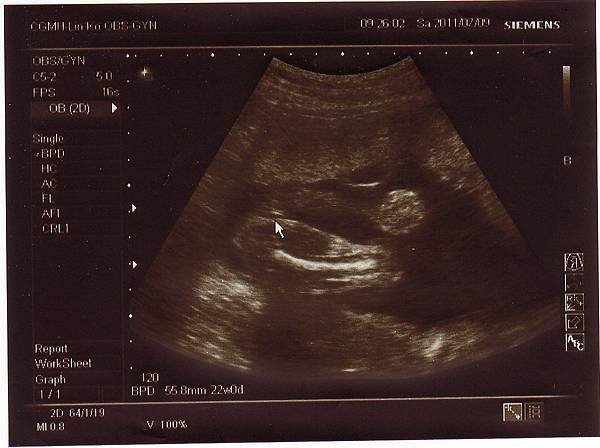

兩個星期後,也就是今天2011.07.09回診了,

還好一切順利,寶寶健健康康的,

醫生說是個長腿妹妹,心跳強而有力,

我懸了兩個星期的大石終於可以放下囉!